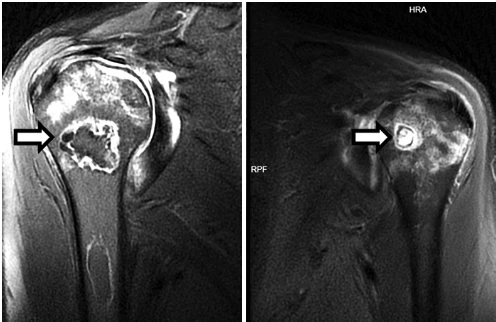

Вот такие плечики у пациента 29 лет! Во время эпидемии COVIDa-19 перенёс тяжёлую форму, лечили, в том числе, высокими дозами кортикостероидов, так что остеонекроз, который мы имеем возможность видеть в головках плечевых костей, по всей видимости, развился, как осложнение этого вида терапии. Хотя, при этой инфекции возникает ещё и гиперкоагуляция, которая и сама по себе является фактором риска развития некроза костей. В литературе такие случаи описаны и известны, есть описания развития остеонекроза даже четырёх костей одновременно (головок бедренных и плечевых костей), причём, развился он аж через полгода после окончания терапии. В нашем случае справа некроз привед к фрагментации головки плеча. Понятное дело, что функции плечевых суставов нарушены, в том числе, за счёт развития грубого вторичного артроза. Видимо, тотальная артропластика потребуется...